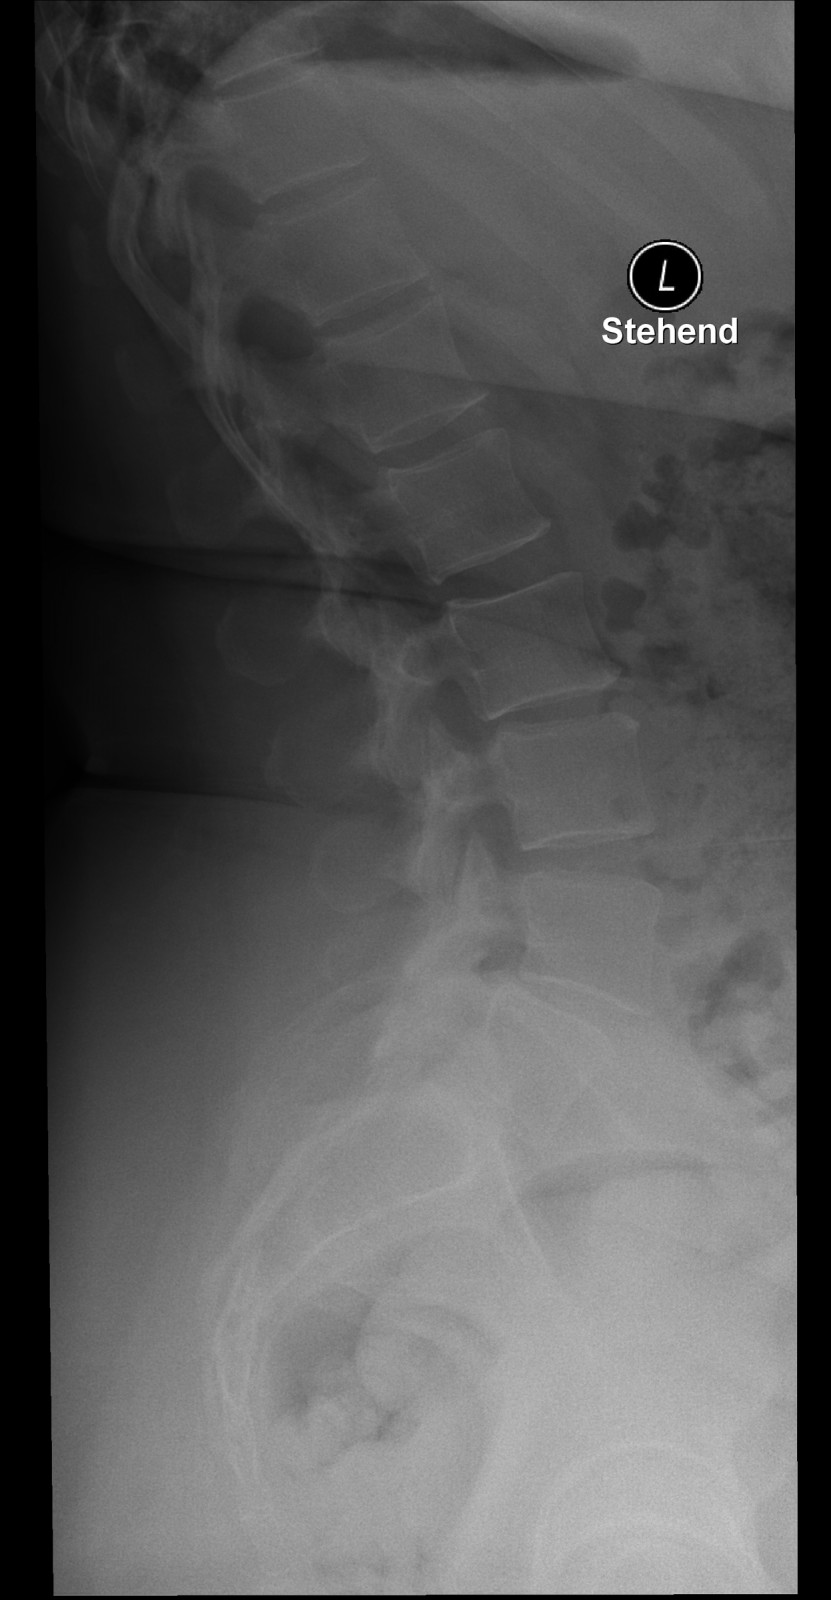

Röntgenfall des Monats Dezember 2017 mit Auflösung

45 jährige Patientin Klinische Angaben: Seit gestern tief lumbale Schmerzen ohne Trauma. Druckdolenz untere LWS und ISG bds.